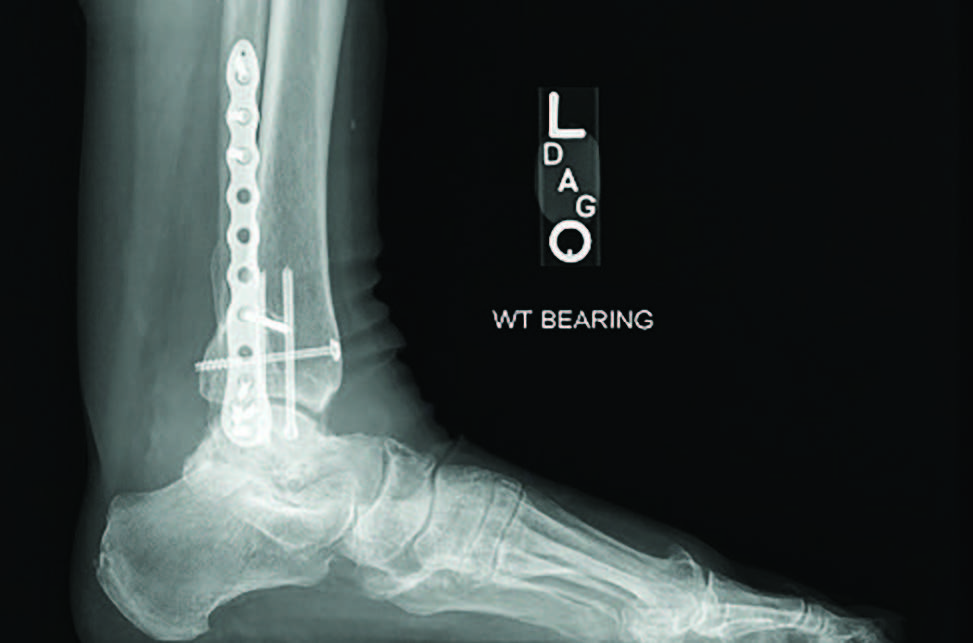

For this patient, I ultimately performed a subtalar joint fusion with distal tibial autograft. She subsequently went on to develop a symptomatic non-union at six months postoperatively and collapse of her talus (see third image above). She again had medical optimization and we planned for a femoral head allograft reconstruction with Augment bone graft and intramedullary nail fixation. The patient went on to clinical success and there was demonstrated healing on a CT scan at four months post-op. She is now weightbearing in a shoe at two years post-op (see fourth and fifth images above).